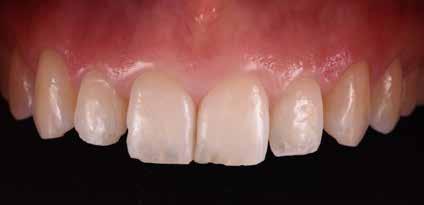

Figg. 236,237 > Faccette in ceramica feldspatica.

Fig. 239 > Dettaglio dell’arcata superiore post-cementazione.

Figg. 240,241 > Immagine intraed extra-orale frontale postcementazione.